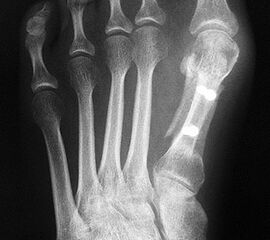

Die dorsoplantaren Röntgenaufnahmen zeigen eine Open-wedge Technik mit der normalerweise ein erhöhter intermetatarsaler Winkel gut zu korrigieren ist (Abbildung 3). Die Wirksamkeit einer Basisosteotomie ist umso größer, je proximaler diese durchgeführt wird. Je weiter distal die Osteotomie, umso geringer die Korrektur. Auf den postoperativen Bildern ist der distal unverändert große Abstand zwischen Metatarsale I und Metatarsale II erkennbar, bei gleichzeitiger Subluxation des Großzehengrundgelenks und dezentrierten Sesambeinen. Darüber hinaus finden sich initiale degenerative Veränderungen im Großzehengrundgelenk. Klinisch bestand eine hohe Weichteilspannung, bei verkürzter Extensor- und Flexor hallucis longus Sehne.  Daher wurde ein verkürzendes Verfahren zur Revision gewählt (Abbildung 4). Die Lapidusarthrodese stellt ein sehr zuverlässiges Verfahren zur Behandlung von Hallux valgus Rezidiven dar 9. Die Fusion des Tarsometatarsale-I-Gelenks kombiniert Stabilität mit einem hohen Korrekturpotenzial. Aufgrund der verfahrensimmanenten Verkürzung des ersten Strahls und der in diesem Fall bereits präoperativ vorhandenen Transfermetatarsalgie wurde die Entscheidung für eine verkürzte Weil-Osteotomie am zweiten bis fünften Strahl gefällt. Die Kombination beider Verfahren führte zu einem homogenen Metatarsale-Index und zu einer gleichmäßigen plantaren Druckverteilung 10. Die Hallux valgus interphalangeus Fehlstellung wurde mit einer Akin-Osteotomie korrigiert.